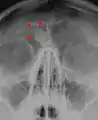

Остеома лобной пазухи на рентгене